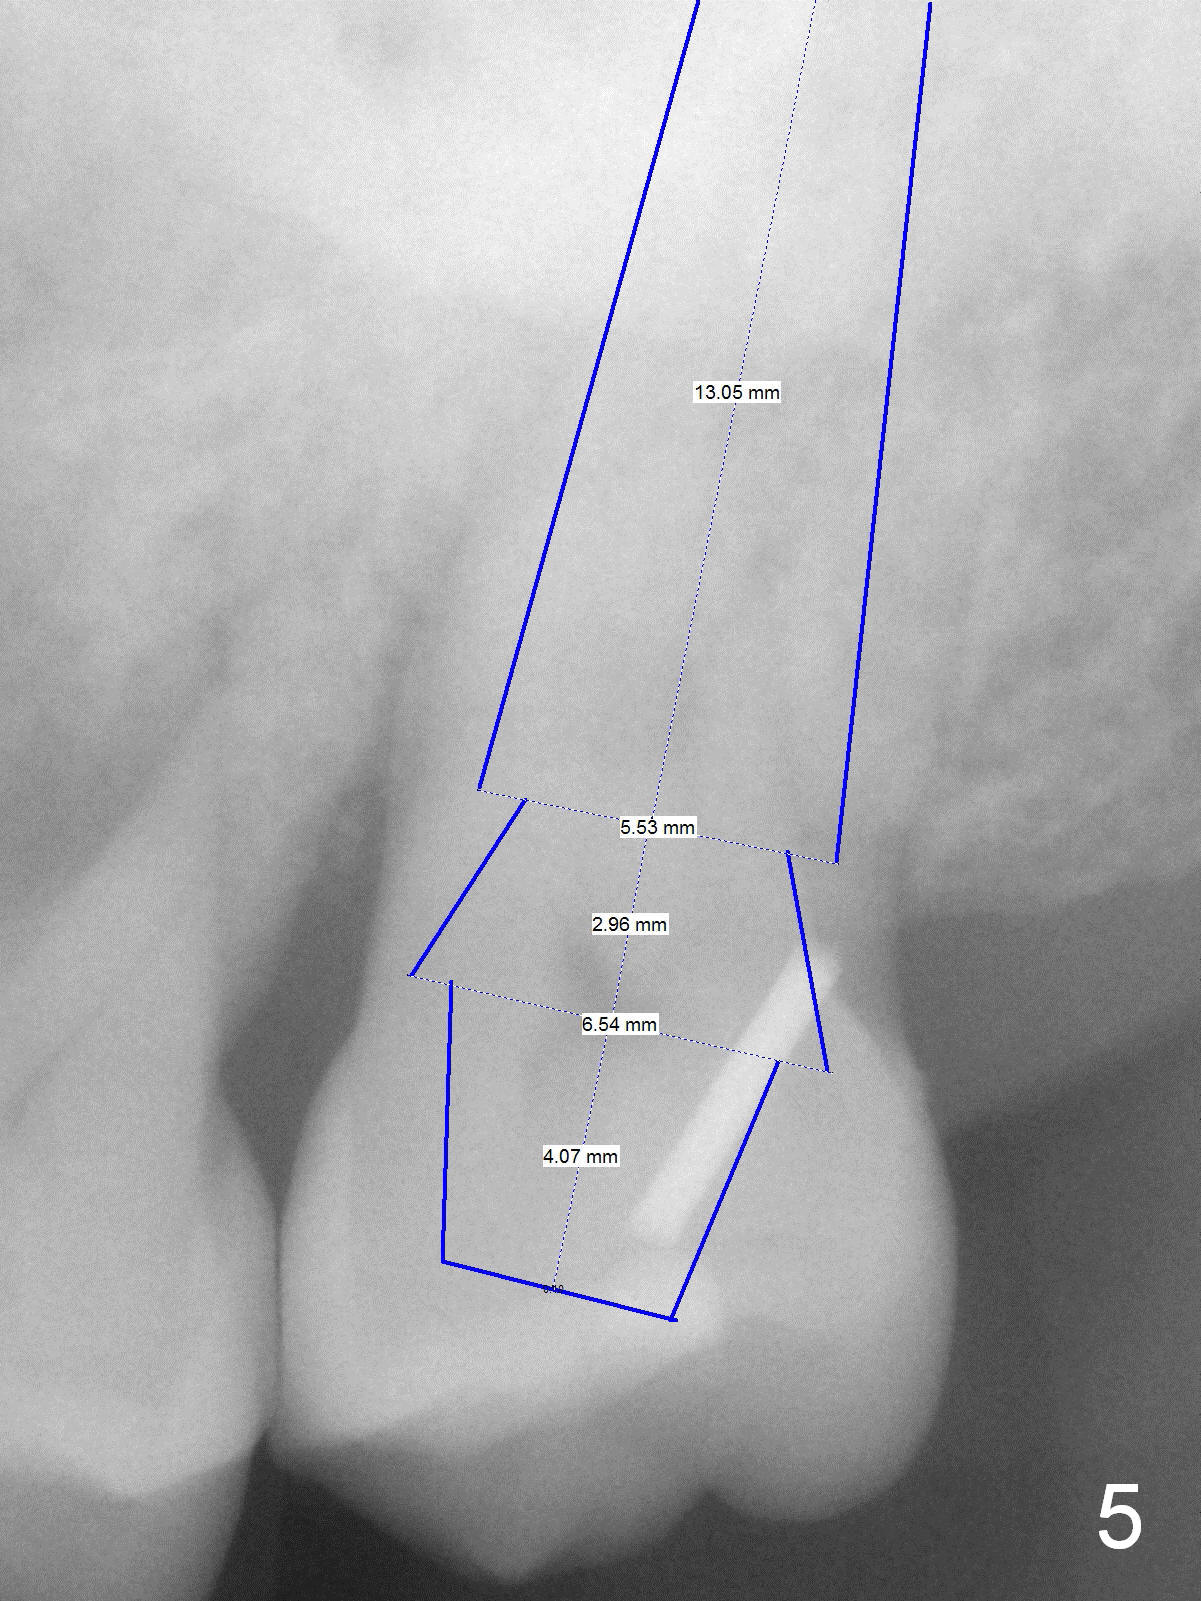

A 54-year-old lady has history of chronic periodontitis, characterized by bone loss (Fig.1 <, 2) . Her oral hygiene is fair. Bone loss and obliterated canals at #14 (Fig.1) are apparently related to bruxism. The latter seems to cause crack tooth at #15 with infection lately (Fig.3). Since the bone height is plenty (Fig.4), the longest implant will be used (5-7x20 mm (tissue-level) or 5.5x13 mm or longer (bone-level, Fig.5)). Use 2 mm drill to measure the socket (Metronidazole) depth and osteotomy will be at least 6 mm in the new bone. In fact, the tooth #14 is found to be affected when the patient returns from a periodontist's office (Fig.3).